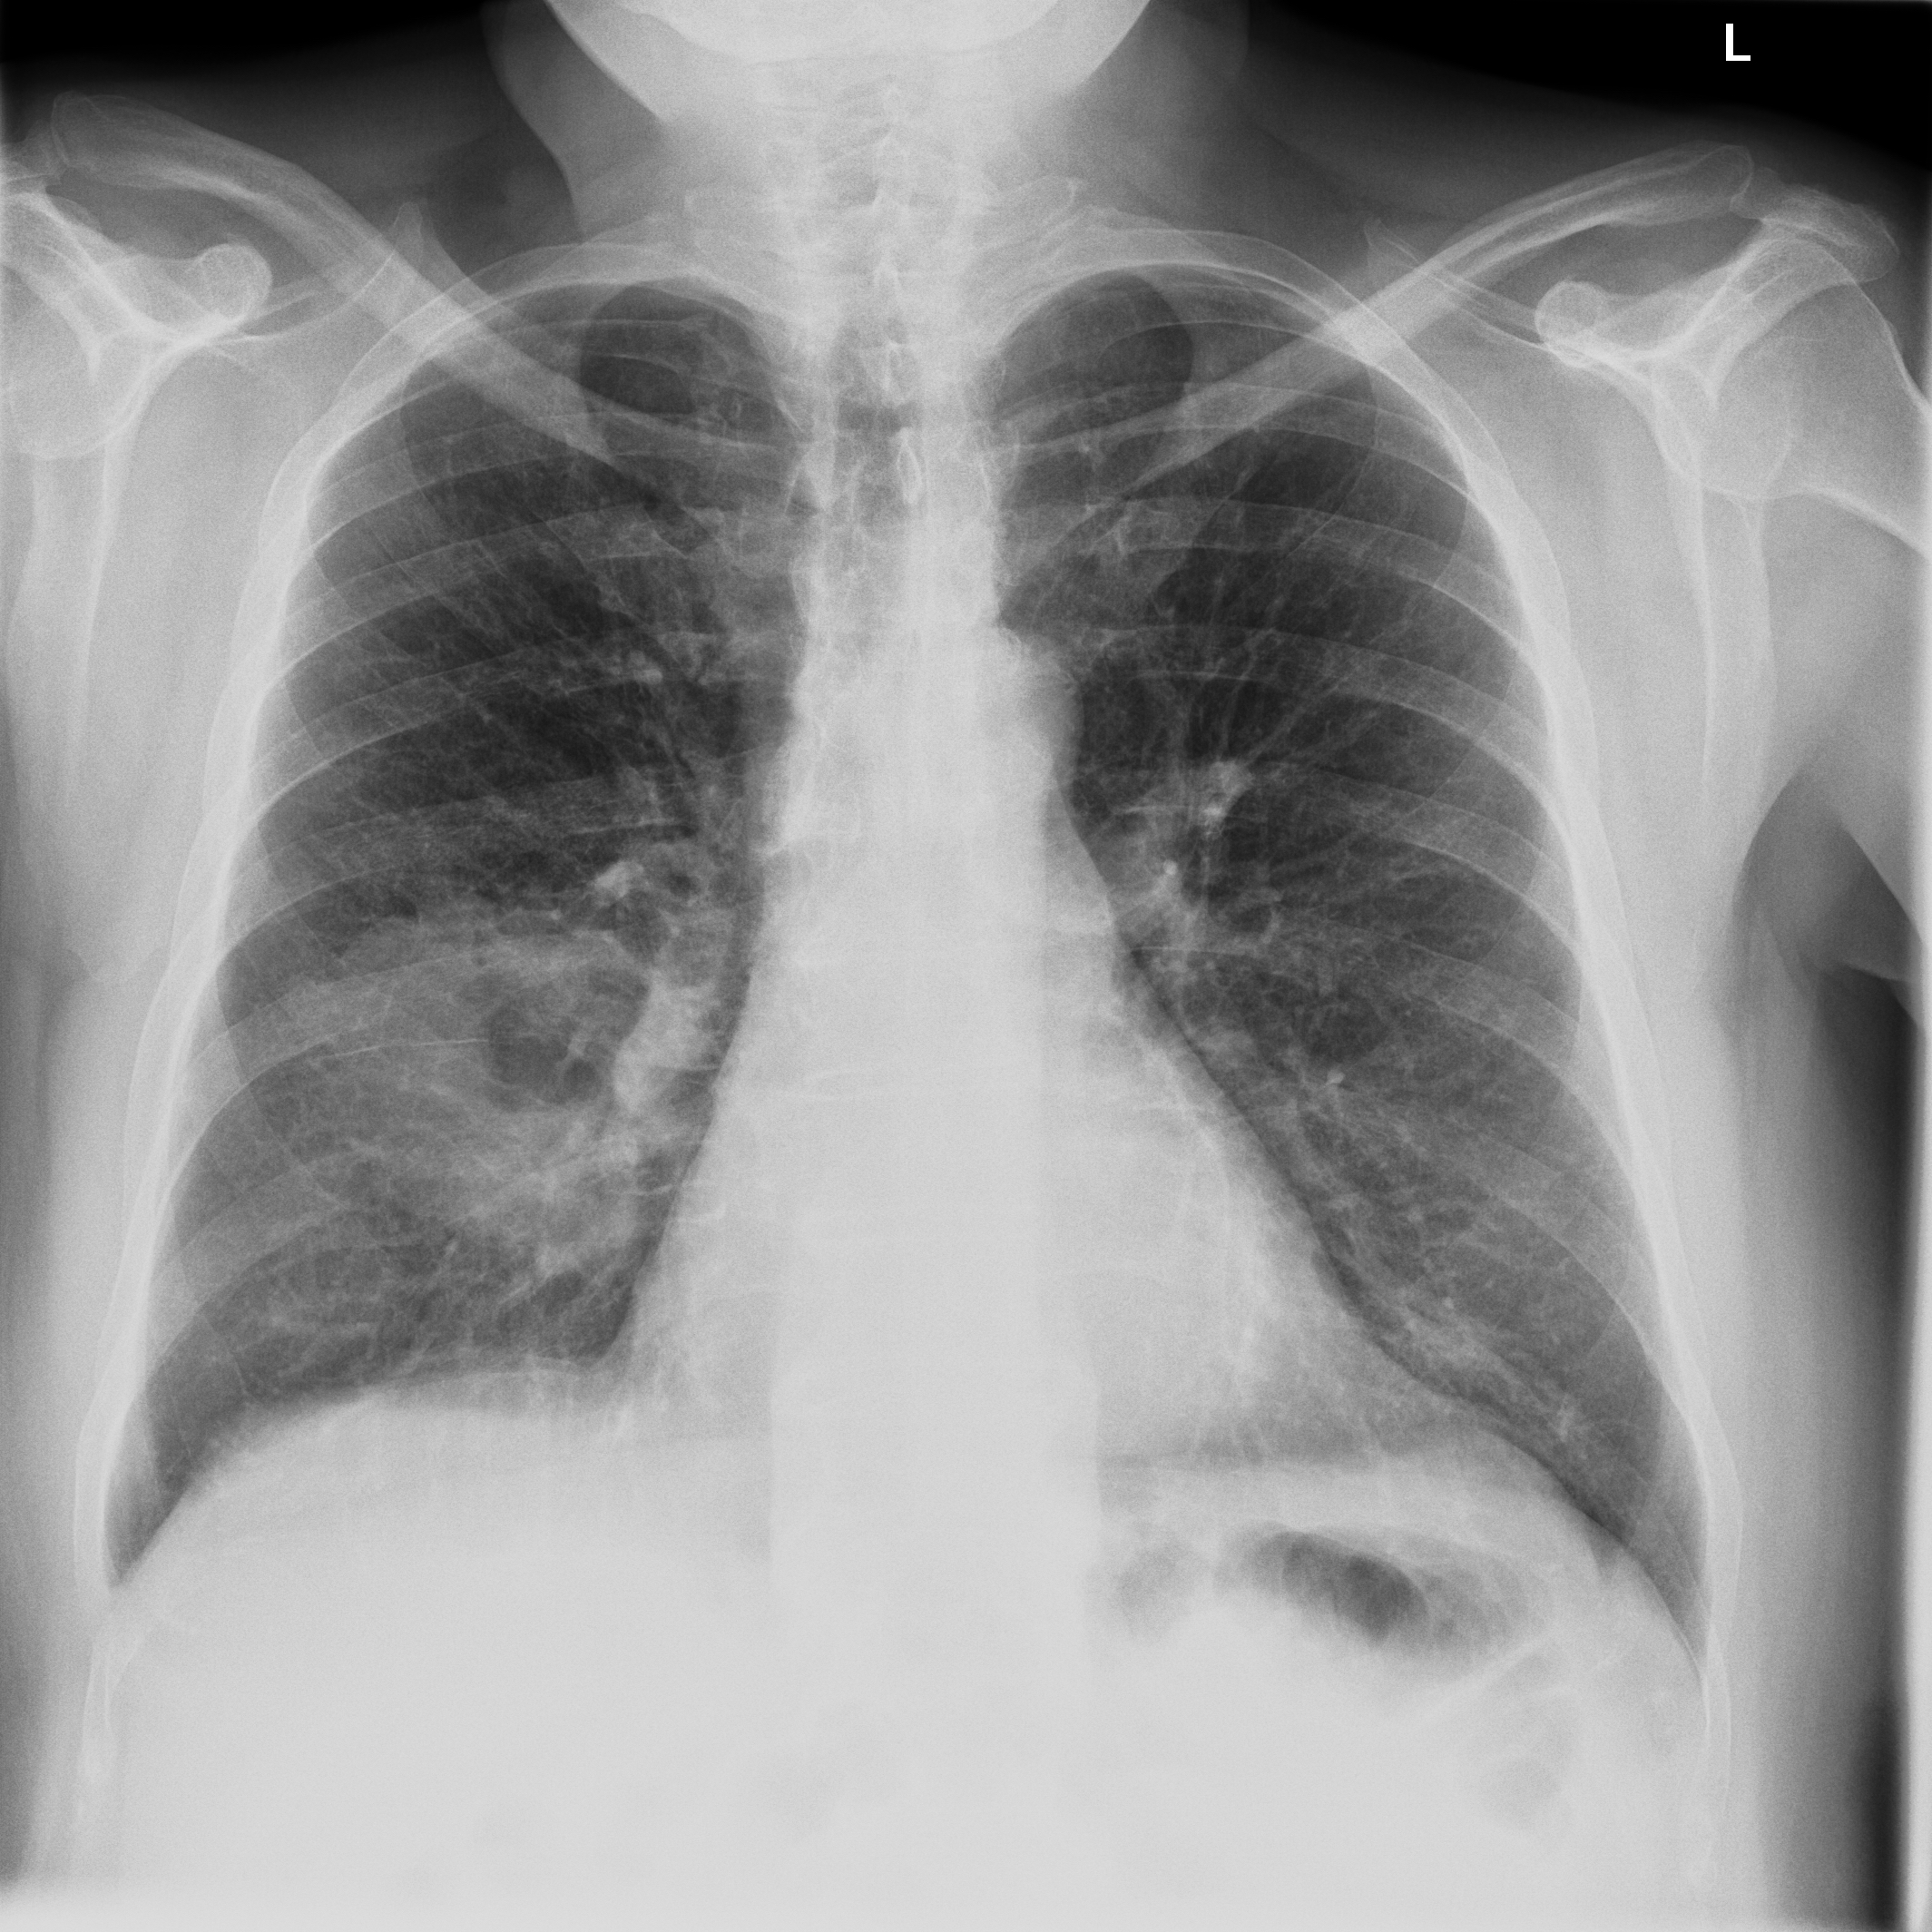

3.3.2 Data

Posteroanterior chest radiographs were acquired on two imaging systems (both Discovery XR656 HD models, GE Healthcare, USA) at Cambridge University Hospitals NHS Trust. Each scanner was being set up in the hospital with different post-processing parameters (chosen by the operating radiologists), which are used here as reference images, see Figure 7 and 8(a). Additional images, serving as real-life examples of lower quality, were produced for each radiographic exposure using multiple different post-processing settings. The post-processing was applied in the hospital directly on the scanner itself by adjusting parameters in the provided framework.

Refer to caption

(a) Reference

(b) (21.1, 0.90, 0.11)

(c) (19.5, 0.88, 0.16)

Figure 7: Chest X-Ray scans with different kinds of post-processing; (a) serves as reference and (b) is wrongly judged as better visualization by PSNR/SSIM/LPIPS.

(b) (22.8, 0.97, 0.08)

(c) (21.2, 0.96, 0.07)

Figure 8: Chest X-Ray scans with different kinds of post-processing; (a) serves as reference, (b) is wrongly judged as better visualization by PSNR and SSIM, LPIPS gives a slightly worse evaluation for (b).

FR-IQA mismatches

In Figure 7, contrast deviation and edge enhancement were reduced in (b), but increased in (c), the noise reduction algorithm was removed in both. The brightness was increased in both images but more so in (c) and low-contrast enhancement was removed in (b). The result is that (b) has relatively low contrast in the lungs compared to the reference (a) and radiograph (c). In Figure 8, edge enhancement has been dramatically increased in (b), whilst the contrast deviation and tissue contrast have been reduced. In (c), the brightness, tissue contrast and edge enhancement have been slightly increased. Consequently, (b) provides low contrast in the lungs with excessively prominent lung markings and vasculature which make it harder to detect abnormalities such as a pneumonia.

All of the chosen FR-IQA metrics wrongly judge (b) as the better image in the first example Figure 7, and the results in (b) and (c) of the second example Figure 8 are quite close, where PSNR and SSIM are also providing the wrong order. The tested measures are not suitable to evaluate the quality of data sets with X-Ray images that have large variations regarding contrast, luminance and sharpness.